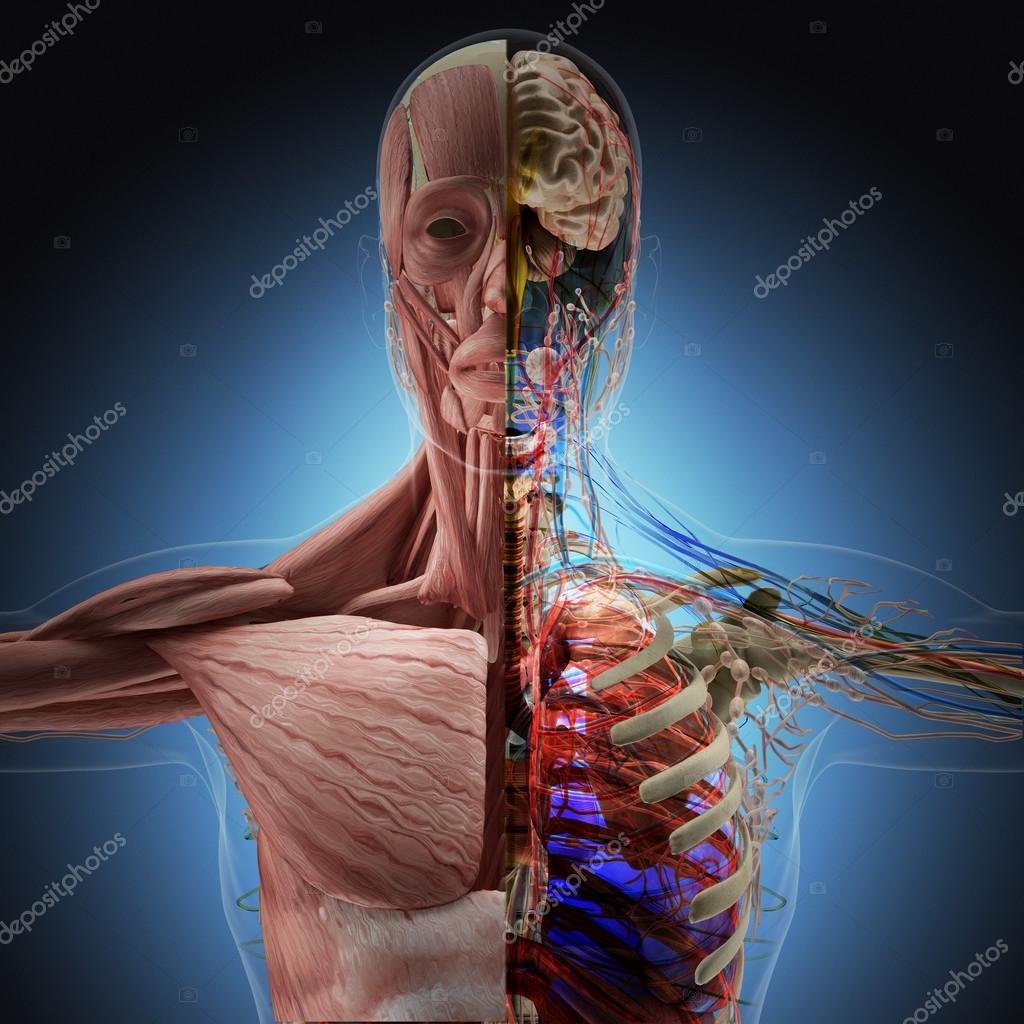

Anatomía De Rayos X Y Cuerpo Humano | Foto Premium

www.freepik.es

www.freepik.es

Anatomía del cuerpo humano en vista de rayos x representación 3d. Cuerpo humano de rayos x con piel transparente representación. La imagen de rayos x del cuerpo humano fotografía de stock